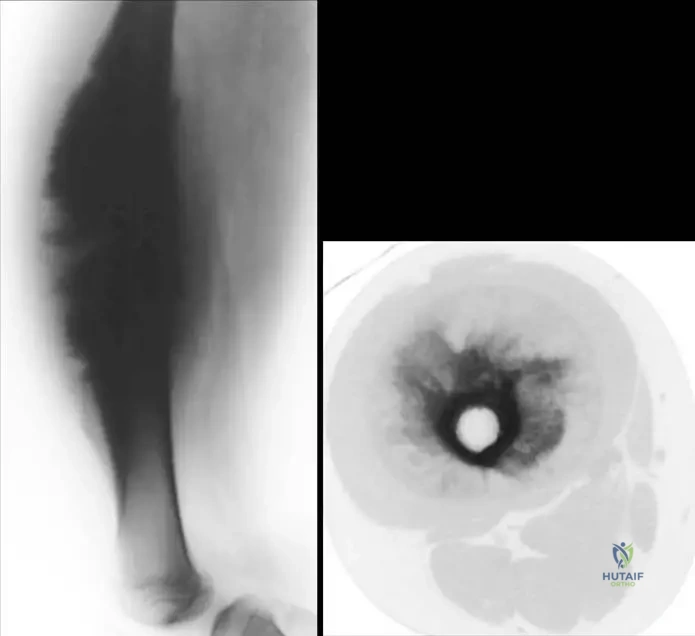

A 17-year-old female presents with a painful mass on her femoral diaphysis. Radiographs and CT scan reveal an incompletely mineralized, circumferential mass on the surface of the bone with abundant periosteal reaction, cortical thickening, and irregularity. The medullary canal appears spared.

Rationale: High-grade surface osteosarcomas are incompletely mineralized lesions occurring on the surface of long bones, frequently with abundant periosteal reaction, cortical thickening, and irregularity. The image (Fig. 8.72 a, b) shows a high-grade surface osteosarcoma of the femoral diaphysis forming a heavily mineralized circumferential mass that encircles the bone but does not involve the medullary canal. This fits the description. Parosteal osteosarcoma is heavily mineralized and typically metaphyseal. Periosteal osteosarcoma is partially mineralized but usually less circumferential and with a distinct unmineralized soft tissue component. Conventional osteosarcoma is intramedullary. Osteoid osteoma is a benign lesion with a small nidus and reactive sclerosis.

A 16-year-old male presents with a painful mass in his femoral diaphysis. Imaging reveals a heavily mineralized circumferential mass that encircles the bone, but importantly, does not involve the medullary canal. This radiographic appearance is MOST consistent with which type of osteosarcoma?

Rationale: The image (Fig. 8.72 a, b) and its caption explicitly state: "Lateral radiograph (a) and axial CT (b) show a high grade surface osteosarcoma of the femoral diaphysis. The lesion forms a heavily mineralized circumferential mass that encircles the bone, but does not involve the medullary canal." This directly matches the vignette. While periosteal osteosarcoma is also a surface lesion, it's typically partially mineralized and less circumferentially encircling. Parosteal is heavily mineralized but usually metaphyseal and not typically circumferential. Conventional osteosarcoma is intramedullary. Osteochondroma is benign and has marrow continuity.